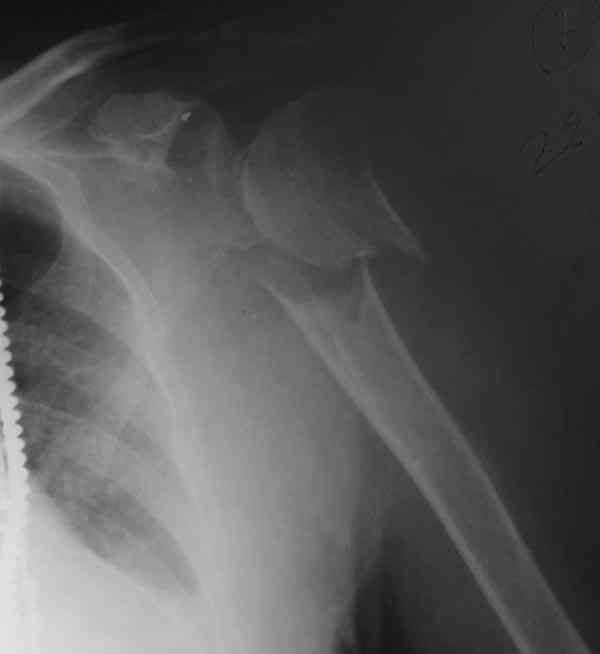

The fracture is completely displaced in the axial view. It is probably possible to align it with the patient in the vertical position, i.e. sitting or standing. However, I would use a locking plate for the tremendous pain relief it offers.

I am attaching the radiographs of the mother of a doctor. She has chronic renal failure for >10 years, diabetes mellitus and coronary artery disease. Age 62. She was offered the options of non-surgical management in a sling and surgery with a locking plate. She was given Tramadol for pain relief. Five days after injury, patient requested surgery, because of pain, inability to move without pain.

The reduction is not perfect. The patient is very small made, and it was difficult to bring the plate proximally without impingement in abduction.

Pain relief after surgery was early and sustained.